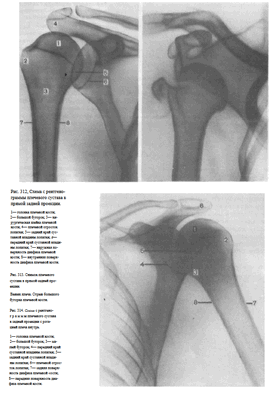

На снимках плечевого сустава хорошо видны головка плечевой кости, суставная впадина лопатки, плечевой отросток лопатки.

На рентгенограмме, произведенной в условиях супинации кисти, хорошо виден большой бугорок плечевой кости, который здесь является краеобразующим (рис.312, 313). На снимках, произведенных в условиях пронации кисти, большой бугорок виден хуже, но по медиальному контуру над хирургической шейкой становится виден малый бугорок (рис.314). Медиальный и латеральный контуры тела плечевой кости при этих двух вариантах укладки на снимках образованы разными ее поверхностями. На снимке при супинации кисти медиальный контур образован внутренней, а латеральный — наружной поверхностью тела плечевой кости; на снимке при пронации кисти медиальный контур отображает переднюю, а латеральный — заднюю поверхность тела плечевой кости.

Информативности снимка. На снимке видны головка плечевой кости, края суставной впадины лопатки, плечевой и клювовидный отростки.

Краеобразующими являются малый бугорок плечевой кости, передняя поверхность диафиза плеча по верхнему контуру и задняя поверхность диафиза плеча по нижнему контуру (рис.318, 319).